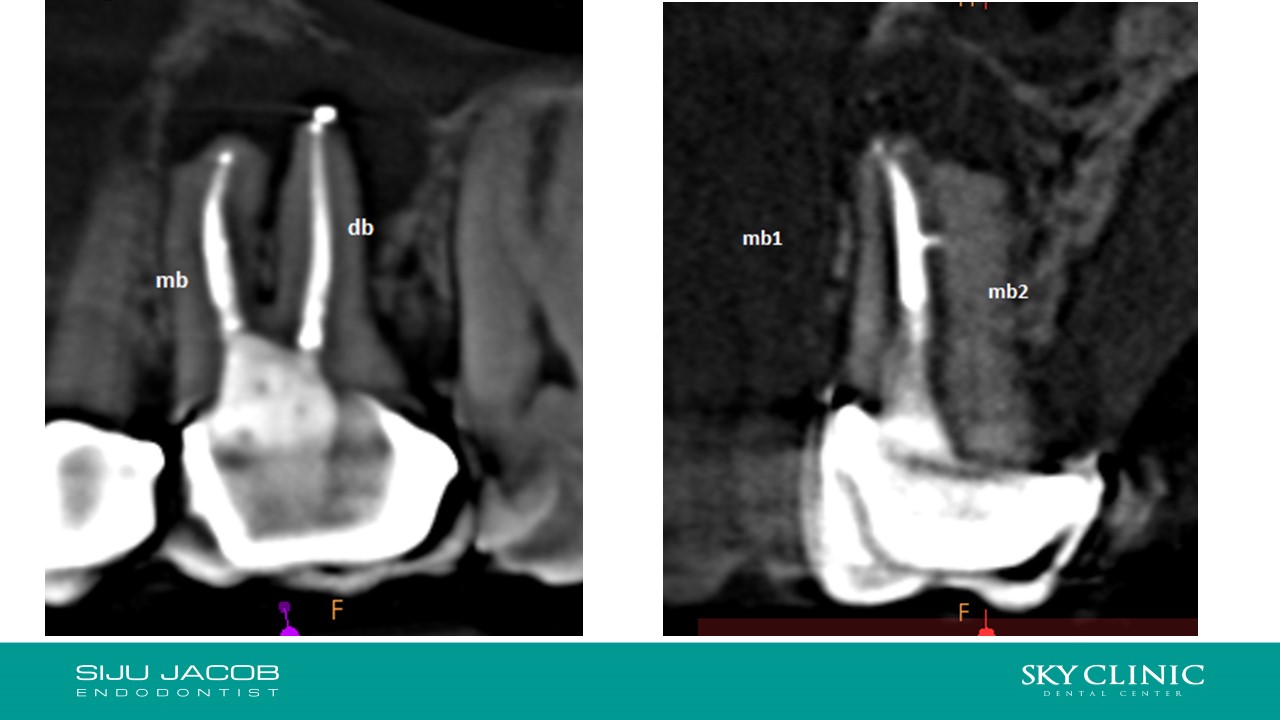

Selective Re-treat of Missed MB2